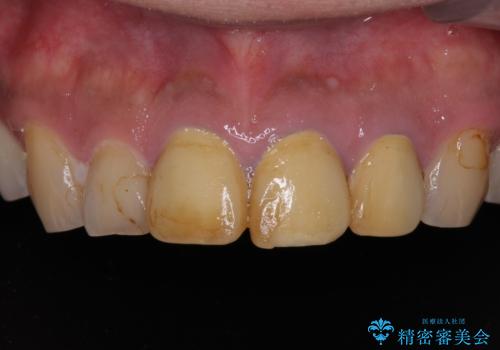

- 黄ばんだ前歯や目立つ奥歯の銀歯をきれいにしたいとのことで来院された患者様です。

小さい修復物の銀歯が装着されている歯はセラミックインレーにて、その他はオールセラミッククラウンにて補綴治療を進めることとしました。